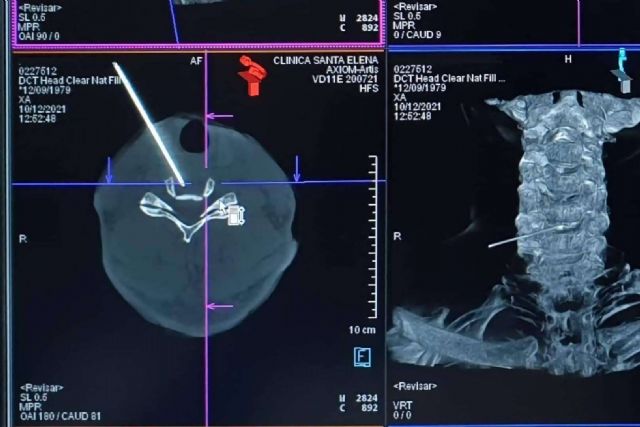

La descompresión discal con láser es un procedimiento mínimamente invasivo que utiliza energía láser, transmitida a través de una aguja, para vaporizar una pequeña porción del disco herniado. Se realiza bajo guía por imágenes y anestesia local. Al disolver y descomprimir parte de la hernia, mejora el dolor y la inflamación en la columna y las extremidades.

De esta manera, esta terapia de una sola sesión no solo resulta muy segura y eficaz para reducir el volumen de la hernia de manera permanente, sino que tiene un menor coste y riesgo respecto a la cirugía. Puede aplicarse tanto a nivel lumbar como cervical.